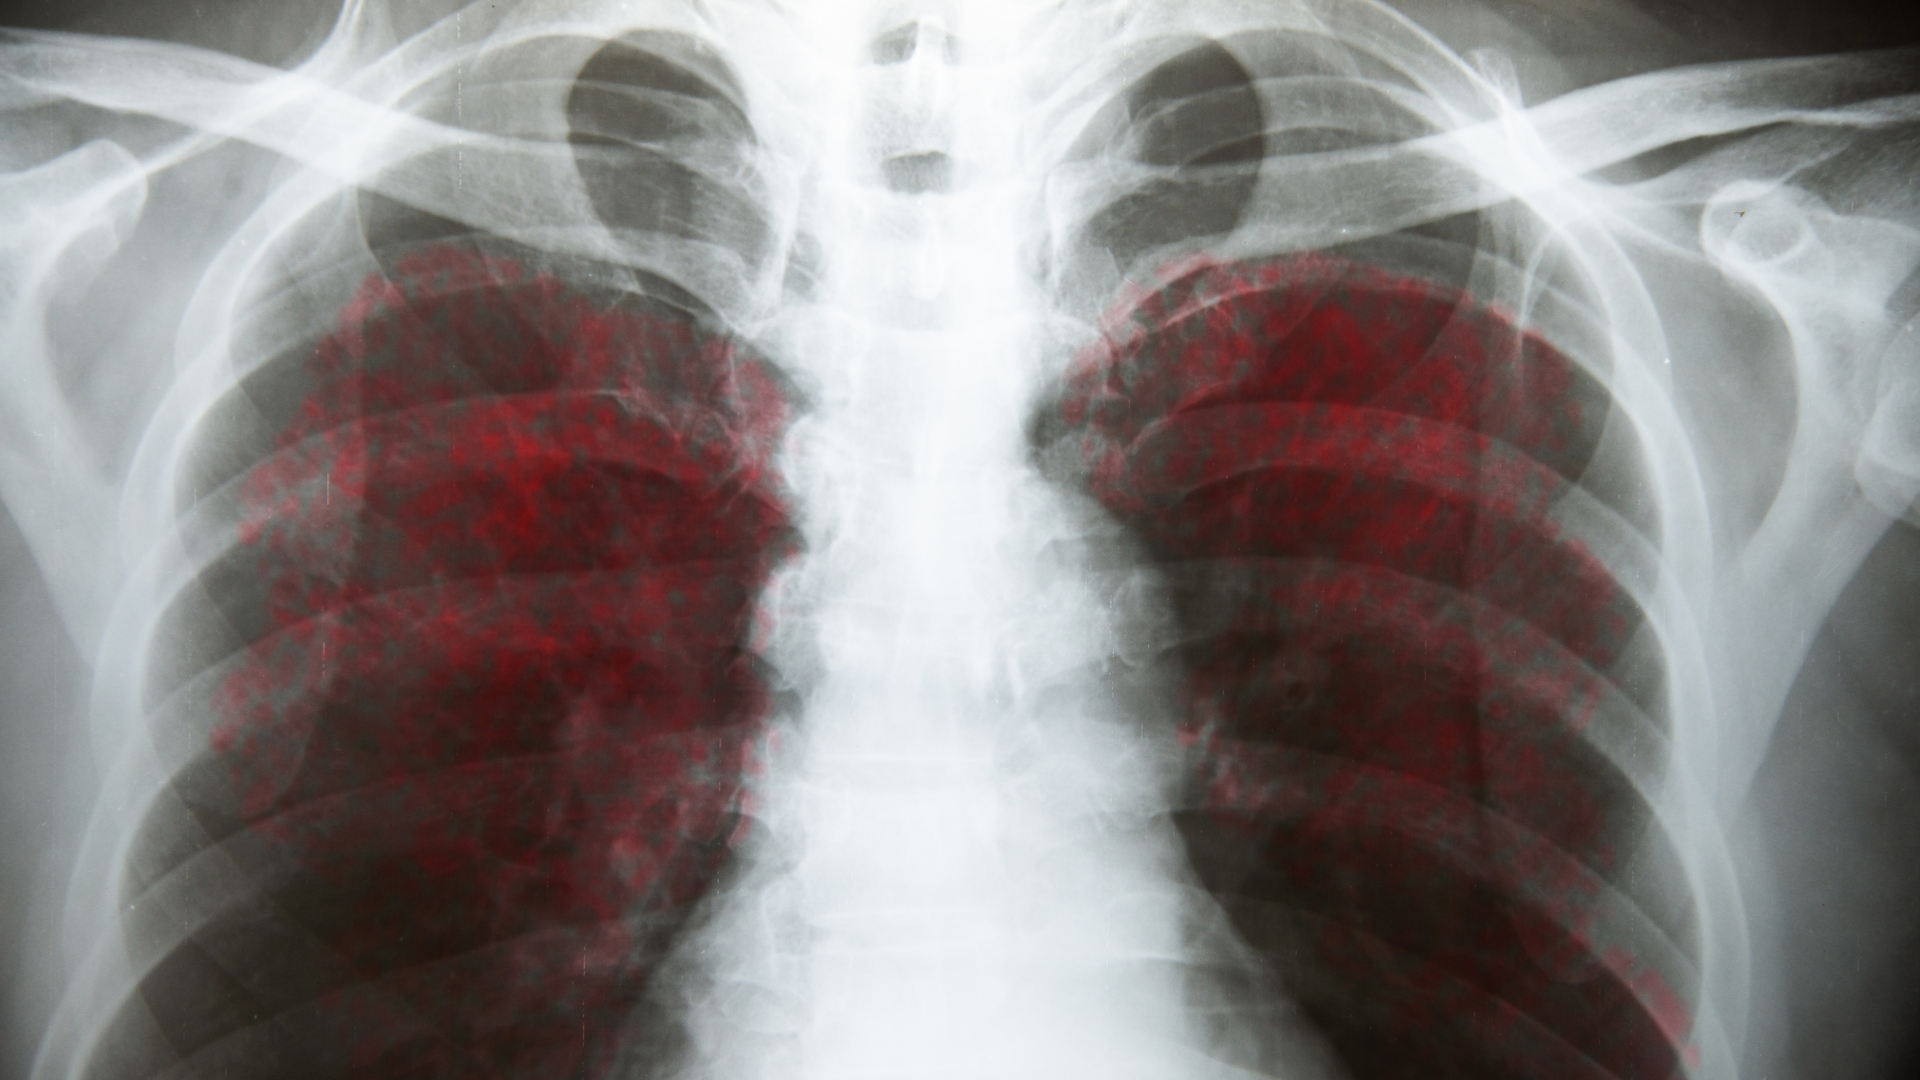

A recent literature review from the Journal of Immunology1 suggests that although the majority of those who contract COVID-19 experience mild to moderate symptoms, the severity of the SARS-CoV-2 infection is associated with dysregulation of inflammatory immune responses. When this hyperinflammatory response (or “cytokine storm”) occurs, it inhibits the development of protective immunity to the infection, and the patient becomes susceptible to sepsis-like inflammation, coagulopathy, and respiratory or cardiovascular complications.

In normal immunity, the innate immune system mounts an immediate inflammatory response to limit the infection and help the adaptive immune system develop long-lasting, host-protective antibodies and T-cell responses against the virus within seven to 10 days postinfection. However, when inflammation is not modulated or resolved after serving its purpose, it develops into hyperinflammation or becomes chronic and results in the inhibition of adaptive immune responses, tissue damage, or organ failure. This dysregulated inflammation results in the major cause of adverse outcomes in SARS-CoV-2–induced COVID-19.